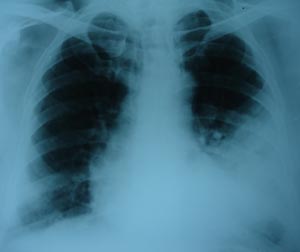

Left pleural effusion2

The radiological appearance of fluid in the pleural cavity are the same regardless of its eteiology whether it is transudate, exudates, pus or blood. The underlying lung pathology may not be seen because the pleural effusion shadow is uniform & homogenous. It lies outside the lung edge & obliterates costophrenic angle. The fluid appears higher laterally than medially.